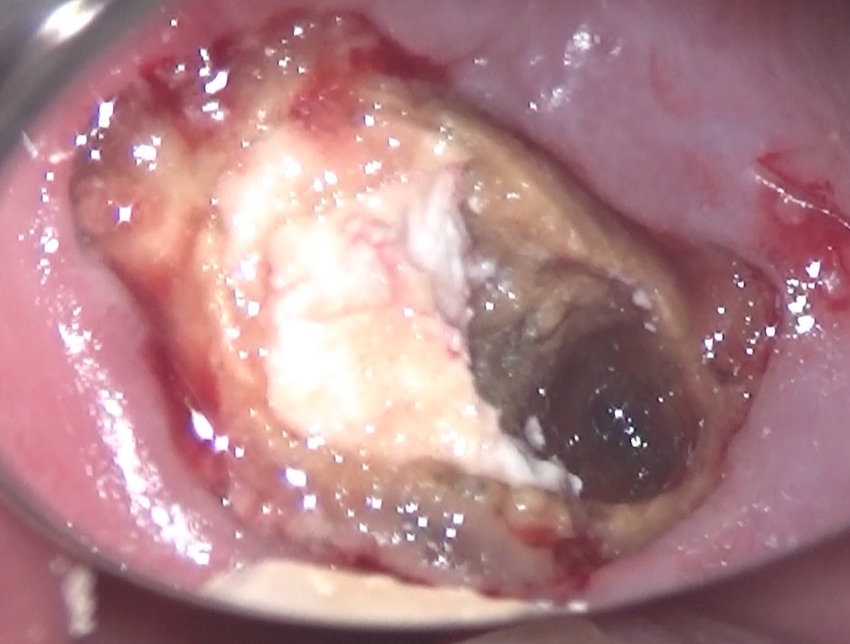

内部を見てみると・・・

内部からは、ニキビを潰した時に出てくるような、体液が出てきています。

特殊なバキュームでその体液を吸引すると、

大きな穴ぼこが空いていました。